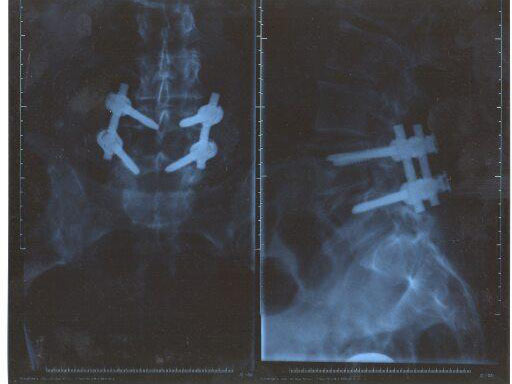

Lumbar degenerative diseases can be treated with pedicle screw and rod fixation devices that provide immobilization and stabilization of the spine during fusion. Minimally invasive techniques are used to reduce tissue trauma and improve patient morbidity and pain, while reducing the length of hospital stay. The less invasive ClickX System provides a mini-open, minimally invasive technique that allows posterior decompression, interbody fusion, and pedicle screw insertion through a smaller lateral incision.

Conditions involving fractures and tumors often require the stabilization of pedicle screws through posterior fusion. The ClickX Monoaxial Screw and Hook System is indicated for stabilization of spinal segments, as an adjunct to fusion, in the treatment of deformity and degenerative diseases. Deformity indications include scoliosis, kyphosis, lordosis, and Scheuermanns disease. Degenerative indications include degenerative disc disease, spondylolisthesis, and stenosis. Monoaxial screws, hooks, rods, and locking caps offer stable fixation to the spine during the bone fusion process.

The top-loading ClickX Monoaxial Pedicle Screw completes the ClickX System. The ClickX Monoaxial Pedicle Screw allows monosegmental spondylolisthesis reduction and can also be used combined with ClickX Polyaxial Screws for multisegmental instrumentation.

The self-tapping screw features dual core design, double lead thread, and rounded tip. The rotatable head is pre-assembled. The screw head can freely rotate around the screw axis, allowing alignment with the rod without adjusting the screw insertion depth. Compared to the Clickx Polyaxial, the profile has been reduced by 2 mm.

The screws are available in diameters of 5.5, 6.2, and 7.0 mm and eight different lengths from 3065 mm. A specific screwdriver and a Holding Sleeve have been designed to pick up the screws from the rack and insert them into the prepared pedicles.